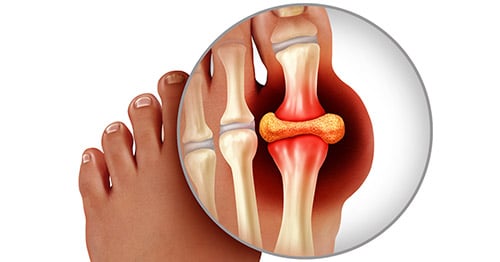

illustration of a normal toe and then one with a gouty tophus

Figure 2: Illustration of Toe Joint with Gouty Tophus. (Left) normal toe joint; (Right) Urate crystals, shown in white, at the "bunion joint," represent a gouty tophus.)